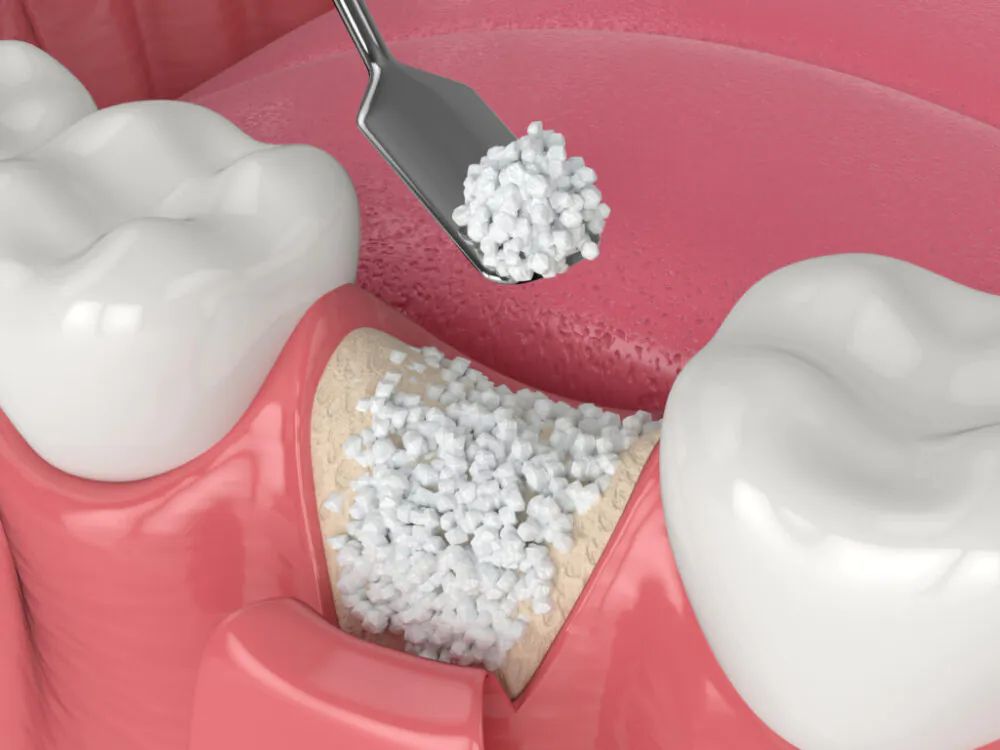

「骨が足りない」とインプラントを断られた方へ

十分な歯槽骨がないとインプラント治療は難しく、骨量不足のために治療を断られることがあります。しかし、デジタル技術を駆使して診査診断を行うと、実際には埋入可能であることがあります。またそれでも厳しそうな場合でも顎の骨量は増やすことが可能です。 当院ではGBR、サイナスリフト、ソケットリフトなどの治療法を用い、骨量が不足している方もインプラント治療を受けられるようにしています。

GBR(骨誘導再生法)

GBR(Guided BoneRegeneration:骨再生誘導法)は、インプラント治療において骨の厚みや高さが不足している場合に採用される歯槽骨再生法です。この手法では、骨形成を妨げる繊維芽細胞の侵入を防ぐため、欠損している骨部分を「メンブレン」と呼ばれる人工膜で被覆します。メンブレン内には自家骨や人工の骨補填材が詰められ、これによって骨芽細胞の増殖が促進されます。 GBRの手法は、骨を再生させてからインプラントを埋入するケースが一般的ですが、場合によってはインプラント埋入と同時に行うこともあります。

サイナスリフト

サイナスリフトは、上顎奥歯のインプラント治療において、骨不足が課題となる際に採用される手法です。上顎の特徴として、上顎洞(サイナス)と呼ばれる空洞が存在し、下顎に比べて骨の厚みが少ないことが挙げられます。 この手法では、歯槽骨とサイナスの間に位置する上顎洞を持ち上げ、そこに人工骨を導入して骨の増加を促進します。手順としては、歯肉を切開し(横から)、骨に穴を開け、サイナスリフトを行います。

ソケットリフト

ソケットリフトは、上顎奥歯部分の骨の厚みが不足している場合に行われる骨再生の手法の一つです。この手法はサイナスリフトと同様、インプラント治療を行う際に十分な骨のサポートが必要な状況で採用されます。 手順としては、まずインプラントを埋入するための穴を開け、その際に同時に人工骨を導入しながら上顎洞を持ち上げていきます。ソケットリフトの特徴は、骨材を導入しながらスペースを作り、直ちにインプラントを埋入する点にあります。これにより、骨を増やす治療とインプラント埋入を同時に行うことが可能で、傷口の大きさや手術時間が短縮され、負担が軽減されるというメリットがあります。